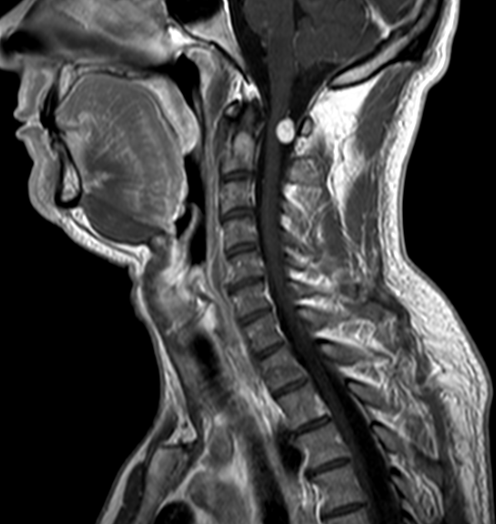

Paciente 34 años que presenta cervicalgia con irradiación a hombro derecho de meses de evolución. En RM cervical se aprecia lesión intradural extramedular informada como schwannoma (menos probable meningioma) a la altura del arco de C1.

Obsérvese la lesión captante, con más tendencia a deformar la médula que a desplazarla (comportamiento que recuerda una lesión intrínseca exofítica)